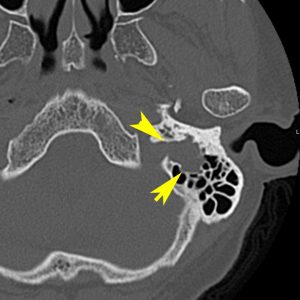

- 側頭骨内にあるものは,MRIよりCT (thin-slice bone-window)の方が正確に進展部位を把握することができます

側頭骨内(顔面神経垂直部)